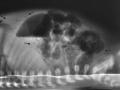

Intubação seletiva em recém-nascido

Dez de 2015.